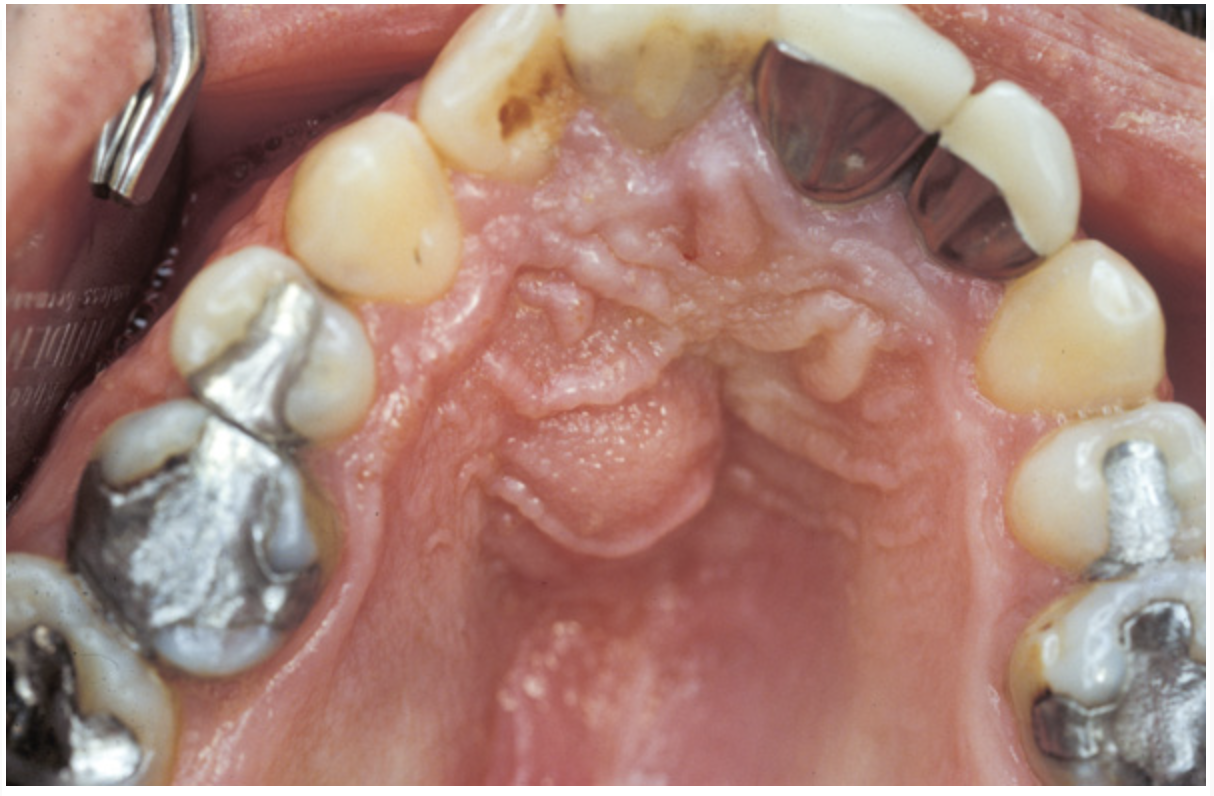

Manifestations of acute infection include abscess and cellulitis. Abscess is an accumulation of pus in an enclosed space7 (Figure 1), while cellulitis is a diffuse inflammatory process within tissues, which may manifest edema, redness, pain, and interference with function (Figure 2). With cellulitis, the infection may be caused by various organisms, and it typically occurs in loose tissues beneath the skin or mucous membranes or around muscle bundles or surrounding organs.7 Also with cellulitis, the severity of the infection is initially determined by virulence of invading bacteria and the host’s response.

Figure 2 Treatment of cellulitis of the submental space consisted first of pulpectomy of teeth Nos. 24 and 25 and intravenous clindamycin. Drainage was complete after 10 days, then endodontic therapy was completed. (Photograph courtesy of Dr. George Romanos.)

Figure 2